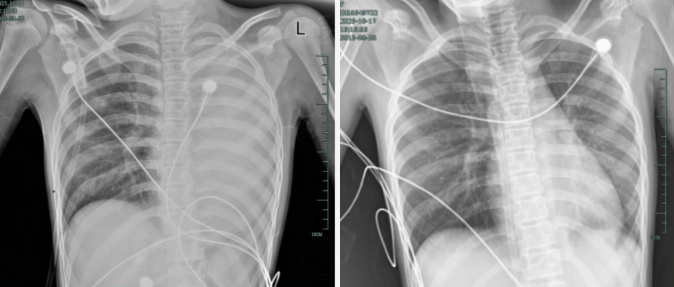

治疗前后影像对比,左肺从“白肺”到正常状态。

据介绍,笑笑一开始只是轻微咳嗽,发热到38℃,检查提示肺炎、肺不张,转诊到浙大四院儿科时,病情已经急剧恶化,出现呼吸急促、胸闷胸痛,体温38.5℃,只能靠5L/min的面罩吸氧维持血氧,胸片显示左肺已完全呈 “白肺” 改变,肺部炎症进展迅猛。

儿科虞琳副主任医师判断,笑笑极有可能是患上了“塑型性支气管炎”。